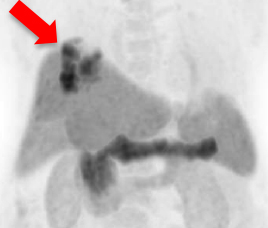

氟18 PSMA正電子/電腦雙融掃描顯示大部分病灶於鑥177 PSMA放射核素治療後可見改善(紅色箭頭所示)。

治療後掃描顯示病灶活躍度大大降低。